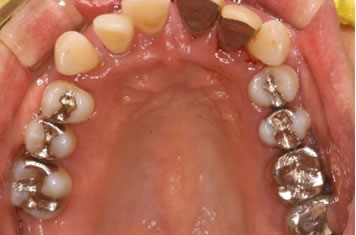

症例3

治療の特徴(患者I様)

初診 2015年5月1日 / 経過 2018年7月2日

| 治療期間 | 2年5カ月(2019年5月時点SPT中) |

|---|---|

| 費用 | 保険内治療 |

| 歯間外科処置 | 1ブロック約9,000円(3割負担) |

| 治療のデメリット | 外科処置を伴う・治療期間が長い(歯槽骨の安定を見る為) 歯周 外科処置後歯肉の位置が下がる為知覚過敏が起こりやすい |